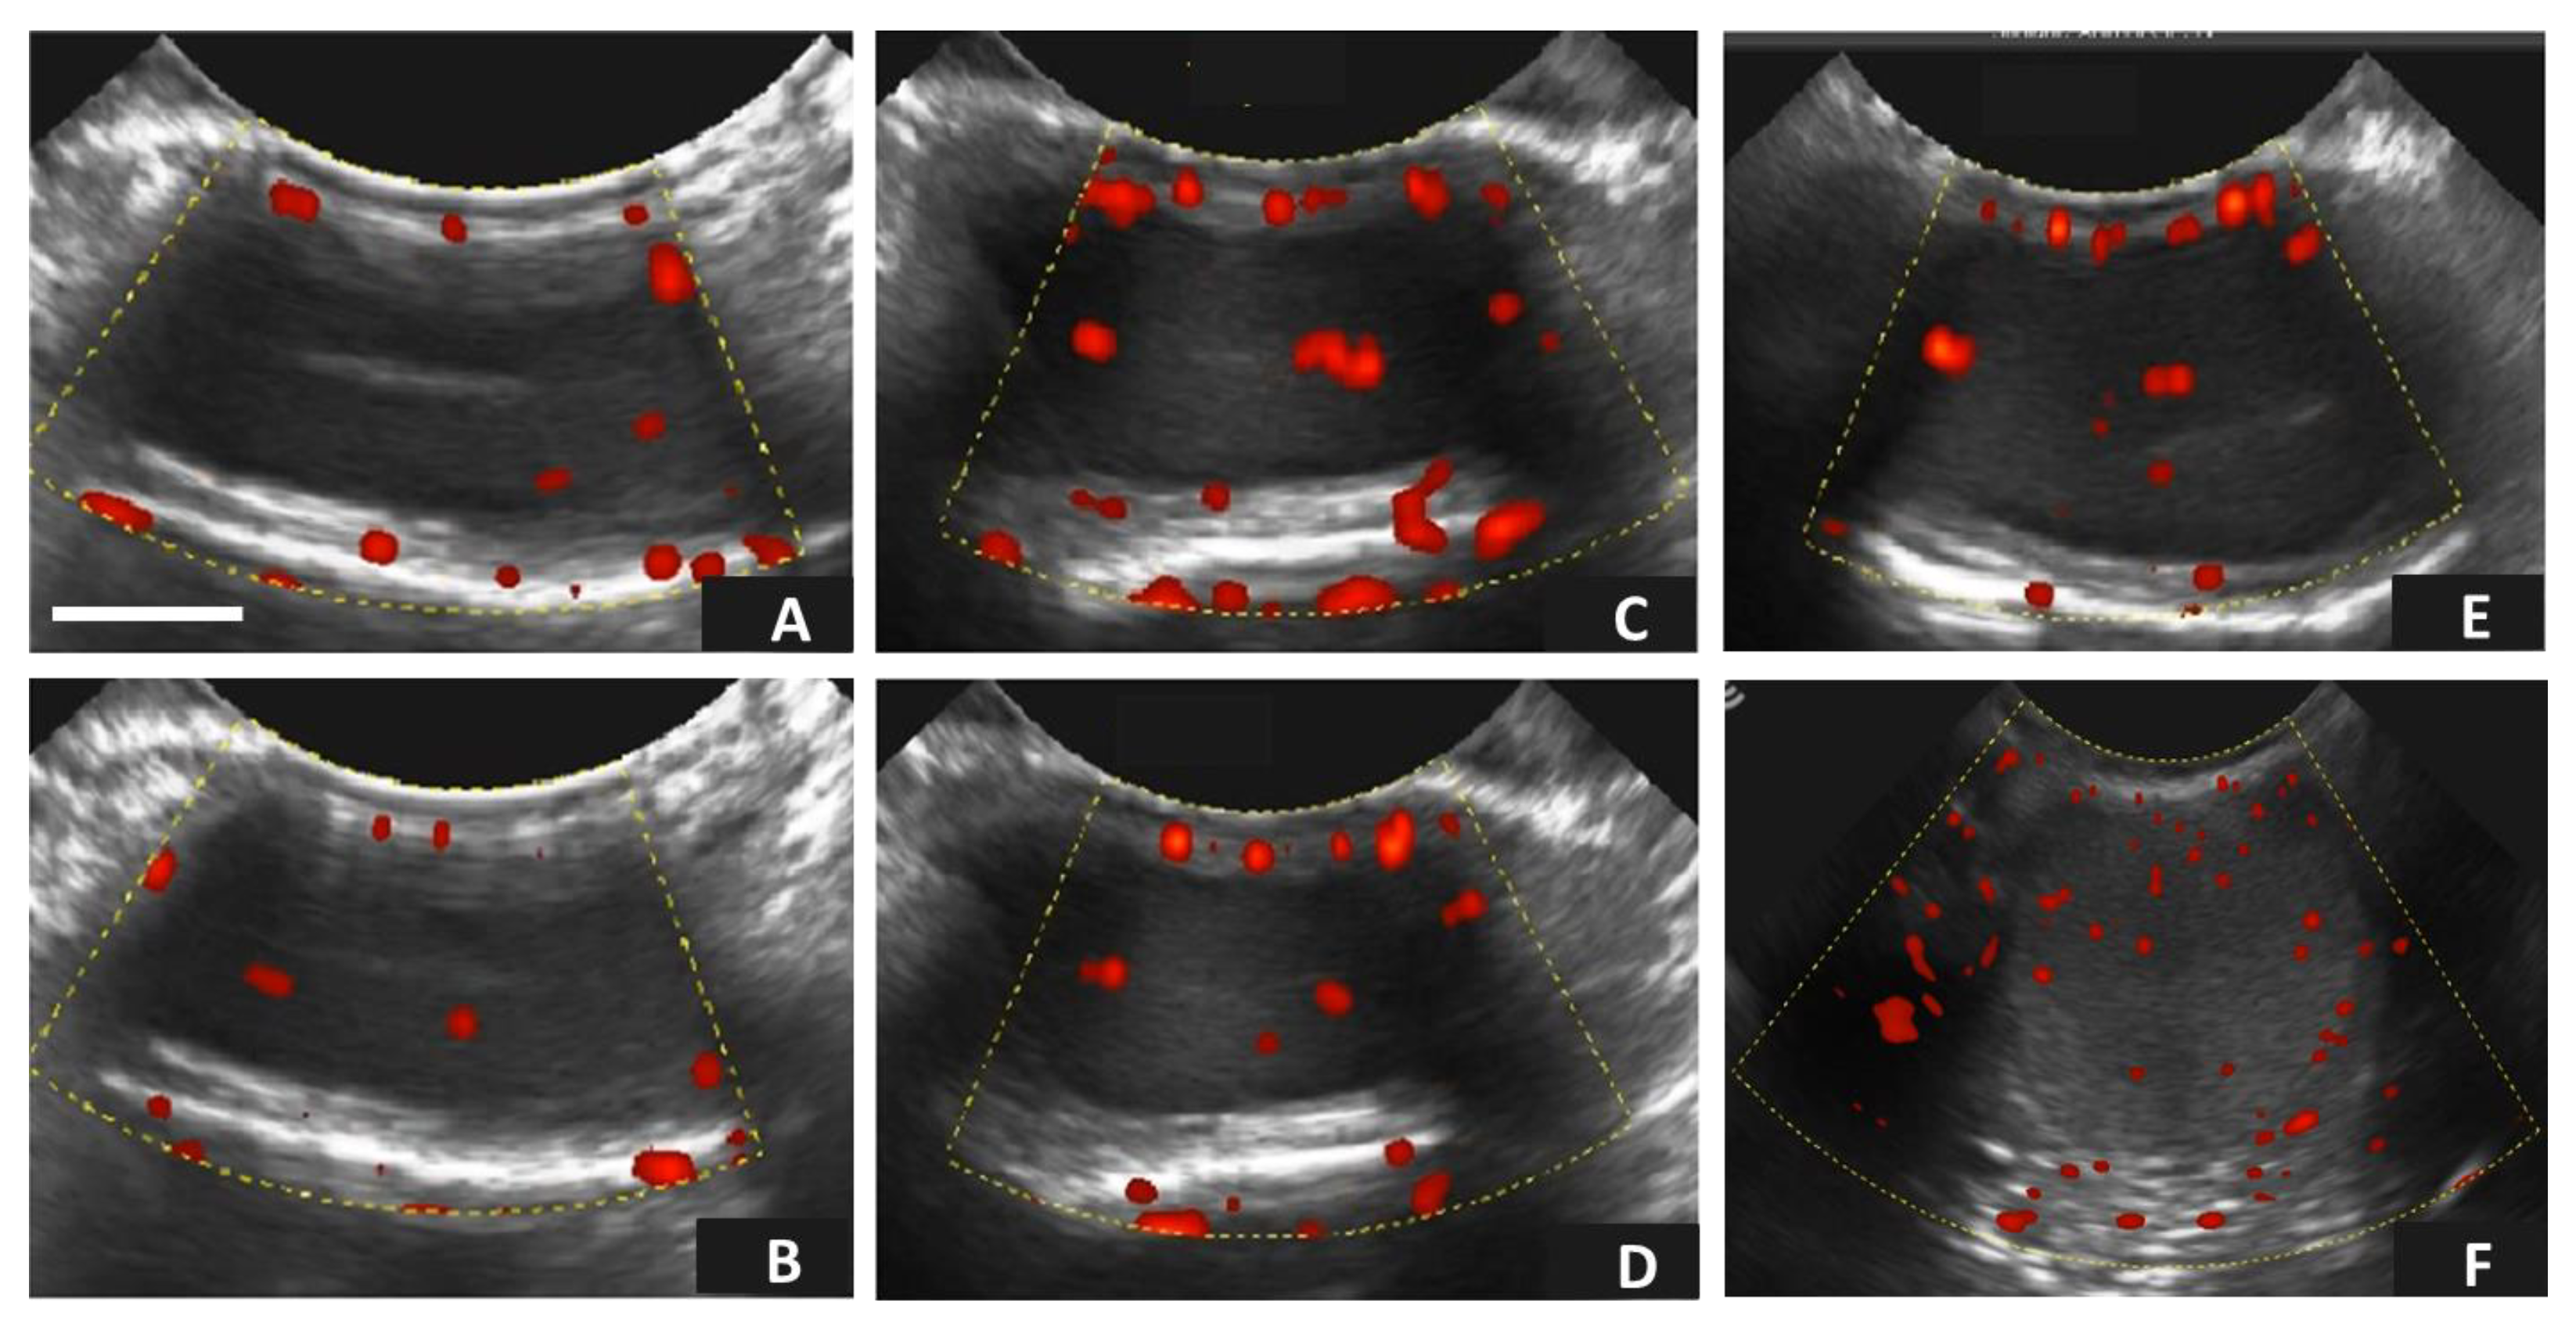

3.2. Age-Related Effects on Testicular Circulatory Dynamics in Alpacas

| Experimental Groups | n | Resistive Index (RI) | Pulsatility Index (PI) | Test. Vascular Area (% TVA) |

|---|---|---|---|---|

| YM (~12–14 mo.) | 5 | 0.54 ± 0.03 | 0.53 ± 0.08 | 9.16 ± 4.83 |

| IM (~24 mo.) | 5 | 0.49 ± 0.06 | 0.31 ± 0.09 | 3.77 ± 0.75 |

| OM (≥36 mo.) | 5 | 0.57 ± 0.05 | 0.47 ± 013 | 3.84 ± 0.25 |